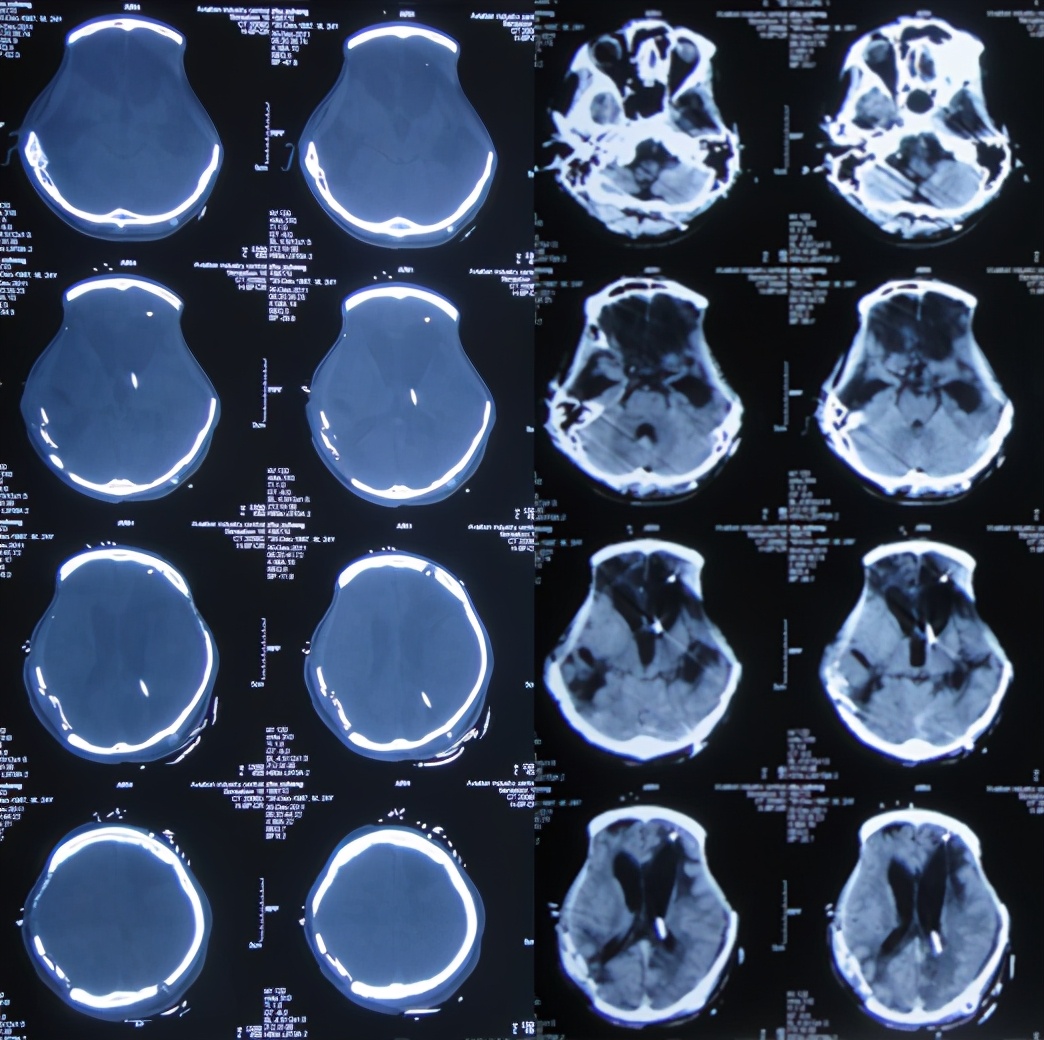

当天急诊去骨瓣减压术;术后当天查头颅CT示双侧去骨瓣减压术后状态( 图-2 )。

图-2: 2011年1月15日术后头颅CT

术后患者生命渐趋稳定;但开颅术后26天即2011年2月10日,复查头颅MRI:轻度脑膨出,脑水肿( 图-3 )。

图-3: 2011年2月10日头颅MRI